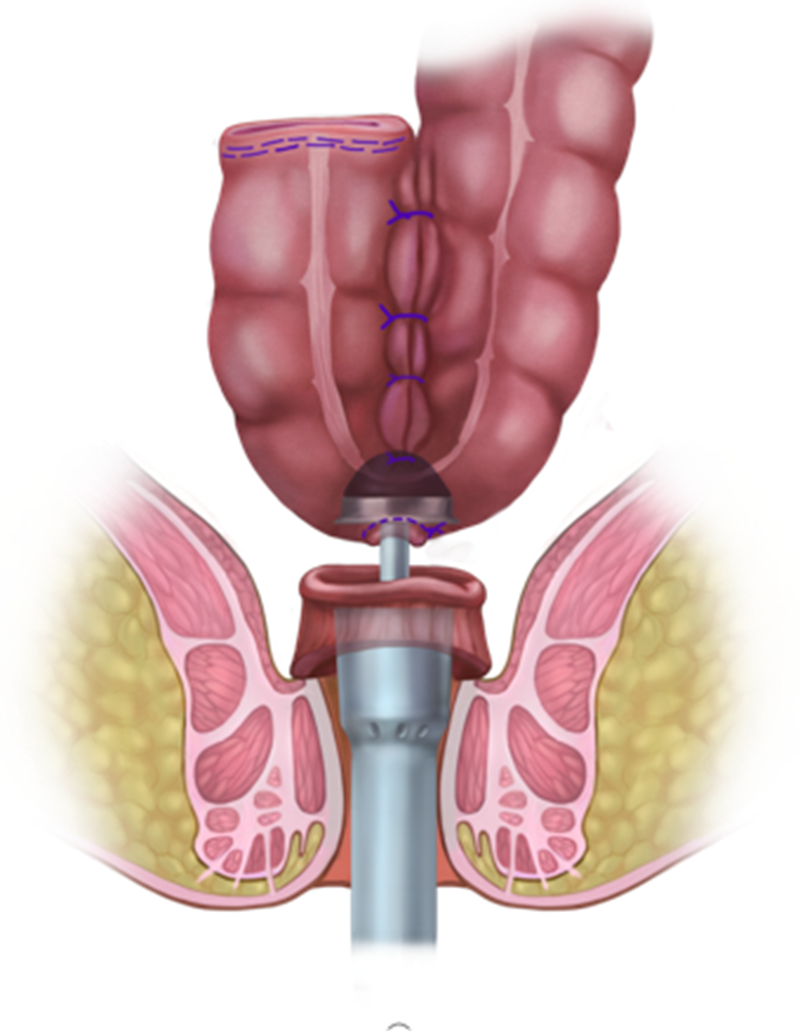

腹腔镜下直肠癌手术

手术前是否需要新辅助治疗、术后是否需要放化疗根据分期决定。病理标本检查常规行免疫组化,指导治疗。